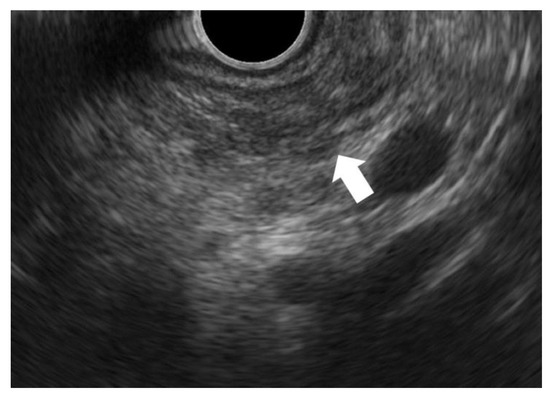

- Terada, S.; Kikuyama, M.; Kawaguchi, S.; Kanemoto, H.; Yokoi, Y.; Kamisawa, T.; Kuruma, S.; Chiba, K.; Honda, G.; Horiguchi, S.; et al. Proposal for Endoscopic Ultrasonography Classification for Small Pancreatic Cancer. Diagnostics 2019, 9, 15. [Google Scholar] [CrossRef] [PubMed]

- Kawaguchi, S.; Kikuyama, M.; Satoh, T.; Terada, S.; Kanemoto, H.; Arai, K. Minimally Invasive Ductal Pancreatic Carcinoma without Low Echoic Area on Endoscopic Ultrasound Examination: A Case Report. J. Jpn. Pancreas Soc. 2017, 32, 852–858, (In Japanese with English Abstract). [Google Scholar] [CrossRef]

- Izumi, Y.; Hanada, K.; Okazaki, A.; Minami, T.; Hirano, N.; Ikemoto, J.; Kanemitsu, K.; Nakadoi, K.; Shishido, T.; Katamura, Y.; et al. Endoscopic Ultrasound Findings and Pathological Features of Pancreatic Carcinoma In Situ. EIO 2019, 7, E585–E593. [Google Scholar] [CrossRef] [PubMed]